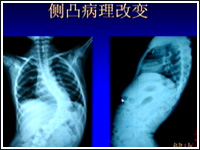

主持人:脊柱侧弯患者的脊柱到底从哪些角度在发生着异常的改变呢? 侯铁胜:青少年发生脊柱侧凸时,脊柱会发生一系列的异常改变,主要表现在两方面:1、脊柱在三维空间发生了变形,如图,脊柱发生了很明显的侧凸畸形,肋骨和胸廓也有畸形,还可以看到很明显的剃刀背的改变。

主持人:手术后效果如何? 李明:脊柱侧弯的病理改变比较复杂,我院从97年开始做脊柱侧弯的三维校正内固定手术,引进了大量先进技术,如图可以看出术后效果是非常不错的。